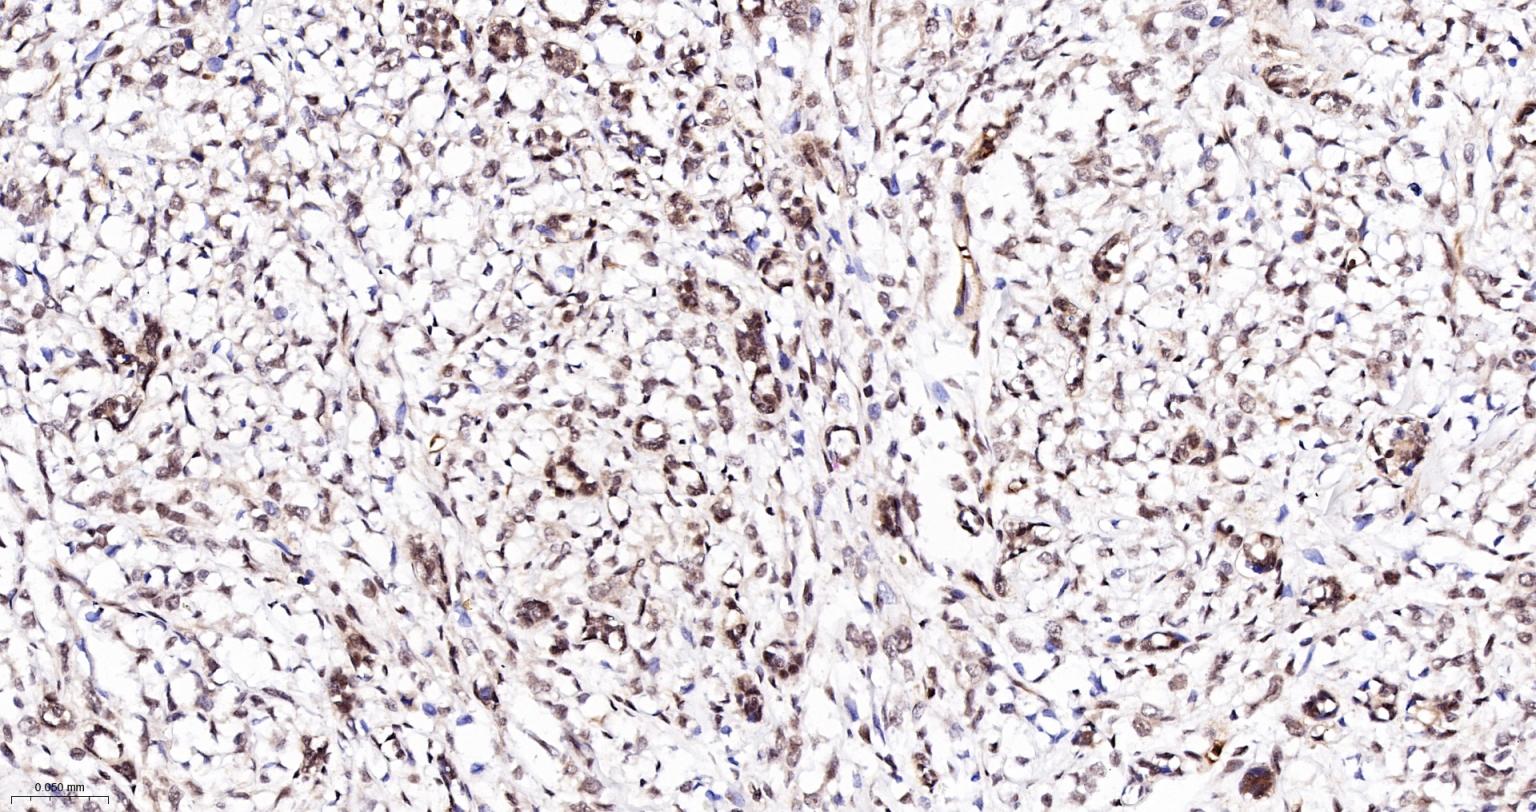

Paraformaldehyde-fixed, paraffin embedded Human Breast Cancer; Antigen retrieval by boiling in sodium citrate buffer (pH6.0) for 15 min; The section was incubated with CTCF Monoclonal Antibody, Unconjugated (bsm-61422R) at 1:200 overnight at 4°C, followed by conjugation to the bs-0295G-HRP and DAB (C-0010) staining.